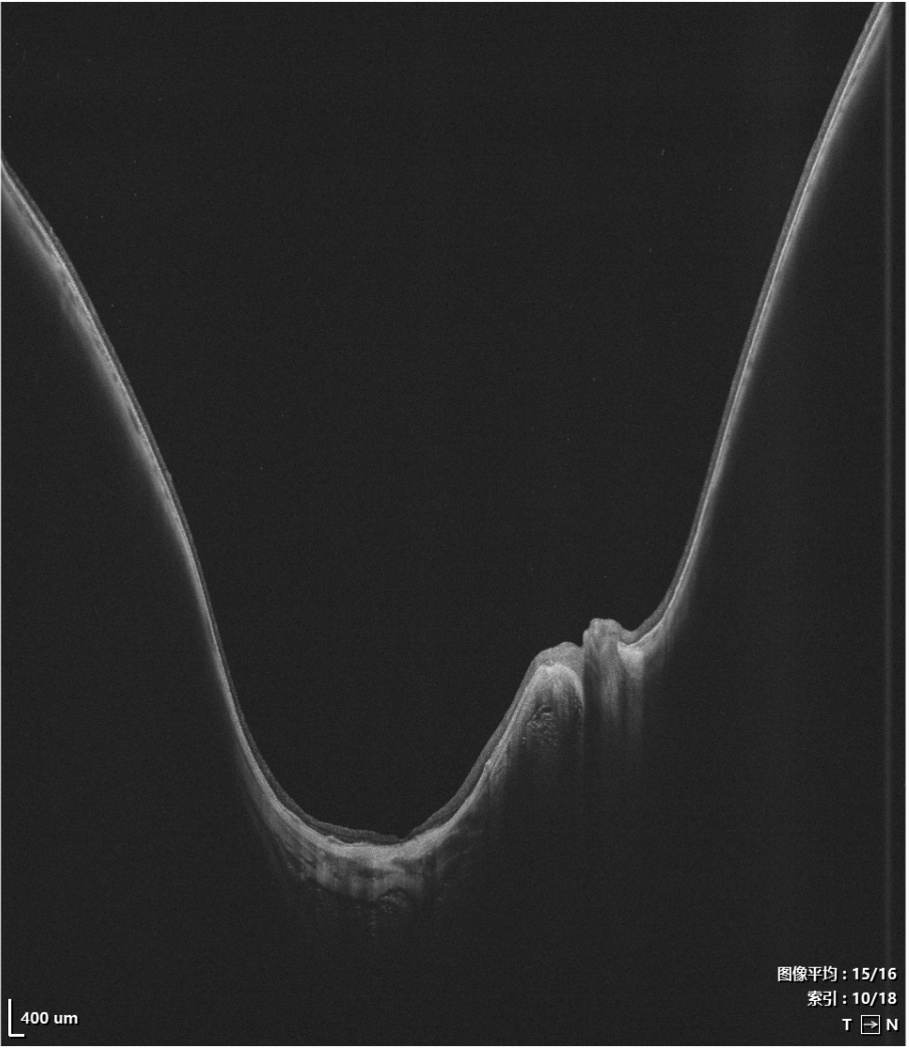

Imaging depth visualization of VG-200I